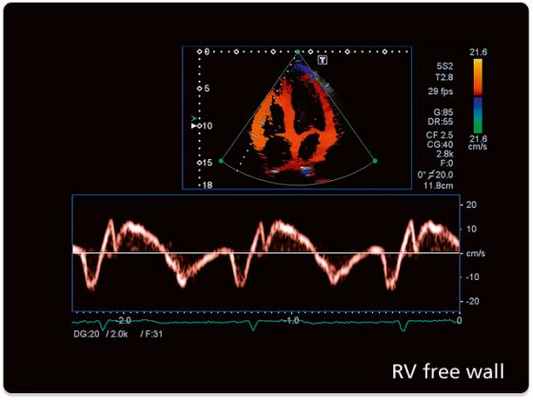

а) Недостаточное выявление потоков из-за проблем с чувствительностью. Многие записи цветовой допплер-ЭхоКГ из апикального доступа не содержат вообще или содержат довольно малоцветокодированной информации в области предсердий. Такое положение дел должно бы вызвать у исследователя критическое отношение к правдивости получаемой информации о потоках крови.

Пример неверной информации. На рисунке ниже слева показан подобный пример, создающий у исследователя впечатление, что у этого пациента с митральной недостаточностью во время систолы в области левого предсердия нет никакого антеградного потока. Однако кардиологу даже с умеренным знанием основных гемодинамических закономерностей известно, что в систолу и раннюю диастолу предсердия интенсивно наполняются из легочных вен и что при неискаженном допплеровском исследовании эти потоки в виде красной, антеградной цветокодированной зоны должны занимать не менее 70% левого предсердия.

То, что часто мы этого не видим, связано с касающимися всех ультразвуковых систем проблемами чувствительности по определению потоков на большой глубине. Но если даже нормальные антеградные потоки не могут быть визуализированы, то это же, к сожалению, относится и к патологическим потокам, диагностике которых и должно бы служить ультразвуковое исследование.

Слева: пример исследования в режиме цветовой допплер-ЭхоКГ (четырехкамерная позиция), где отсутствует информация о потоках крови в области предсердий у пациента с дилатационной кардиомиопатией и митральной недостаточностью.

Справа: после контрастного усиления, благодаря которому визуализируется как патологический (большая струя регургитации), так и нормальный антеградный кровоток (красный цвет).

На рисунке ниже справа показано изображение того же пациента: при контрастном усилении допплеровское исследование выявляет широкую, проходящую через все предсердие струю митральной регургитации наряду с ангеградным ламинарным потоком. То, что контрастное усиление не ведет к искажающему увеличению струи регургитации, было доказано при сравнении этого режима с чреспищеводным неконтрастированным допплеровским исследованием, и это позволяет достичь существенно более надежной оценки степени тяжести митральной недостаточности.